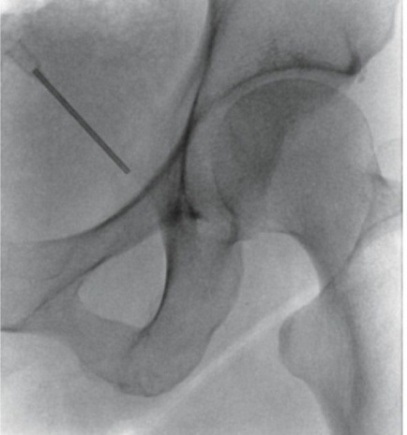

Πρόκειται για δυο τεχνικές που στοχεύουν στη διακοπή της μετάδοσης των σημάτων πόνου κατά μήκος των νευρικών οδών. Η πρώτη μέθοδος χρησιμοποιεί ραδιοσυχνότητες για να το πετύχει αυτό και η δεύτερη υγρό άζωτο που είναι ψυκτικός παράγοντας. Εφαρμόζονται σε ξύπνιο ασθενή με τοπική αναισθησία και κάτω από ακτινοσκοπική καθοδήγηση. Προσφέρουν σημαντική ανακούφιση για μήνες και επαναλαμβάνονται ως πράξεις εάν χρειασθεί μετά το πέρας της διάρκειας δράσης.